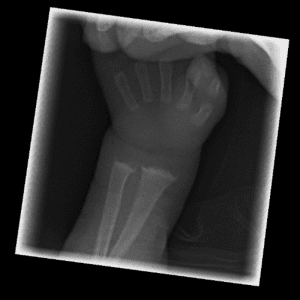

Pediatric Radiographs